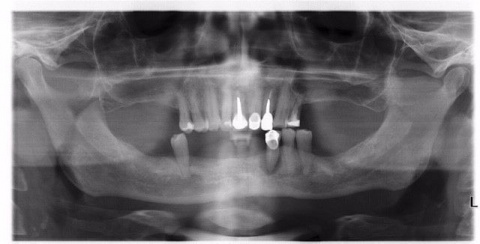

Dr. Inge De Latte beschreibt das klinische und labortechnische Vorgehen bei der Sofortversorgung eines zahnlosen Unterkiefers mit einer verschraubten zirkulären Brücke auf zwei geraden und zwei angulierten BLX Implantaten nach dem Pro-Arch Konzept. Die Implantate wurden bereits am Tag der Operation belastet, was durch deren spezifische Eigenschaften erleichtert wurde.

Ein ausreichendes Restknochenvolumen und eine ausreichende Knochenqualität sind wichtige Voraussetzungen für die erfolgreiche Versorgung nach den entsprechenden Konzepten. Je nach Patientensituation kann der vorhandene Knochen durch angulierte Implantate im Seitenzahnbereich, [4], durchmesserreduzierte Implantate [5] oder kurze Implantate [6] optimal genutzt werden.

Die entsprechenden Protokolle sehen die Verwendung von vier oder sechs interforaminalen oder anterioren Implantaten vor, unter Umgehung der Kieferhöhlen und des unteren Seitenzahnbereich (all-on-four) [7,8].